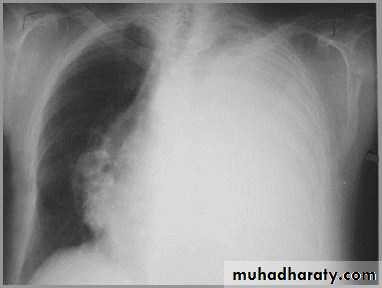

Differentiating the Causes of an Opacified Hemithorax

Atelectasis of an entire lungA large pleural effusion

It acts like a massPushing the heart and trachea away from the side of opacification

Pleural effusion